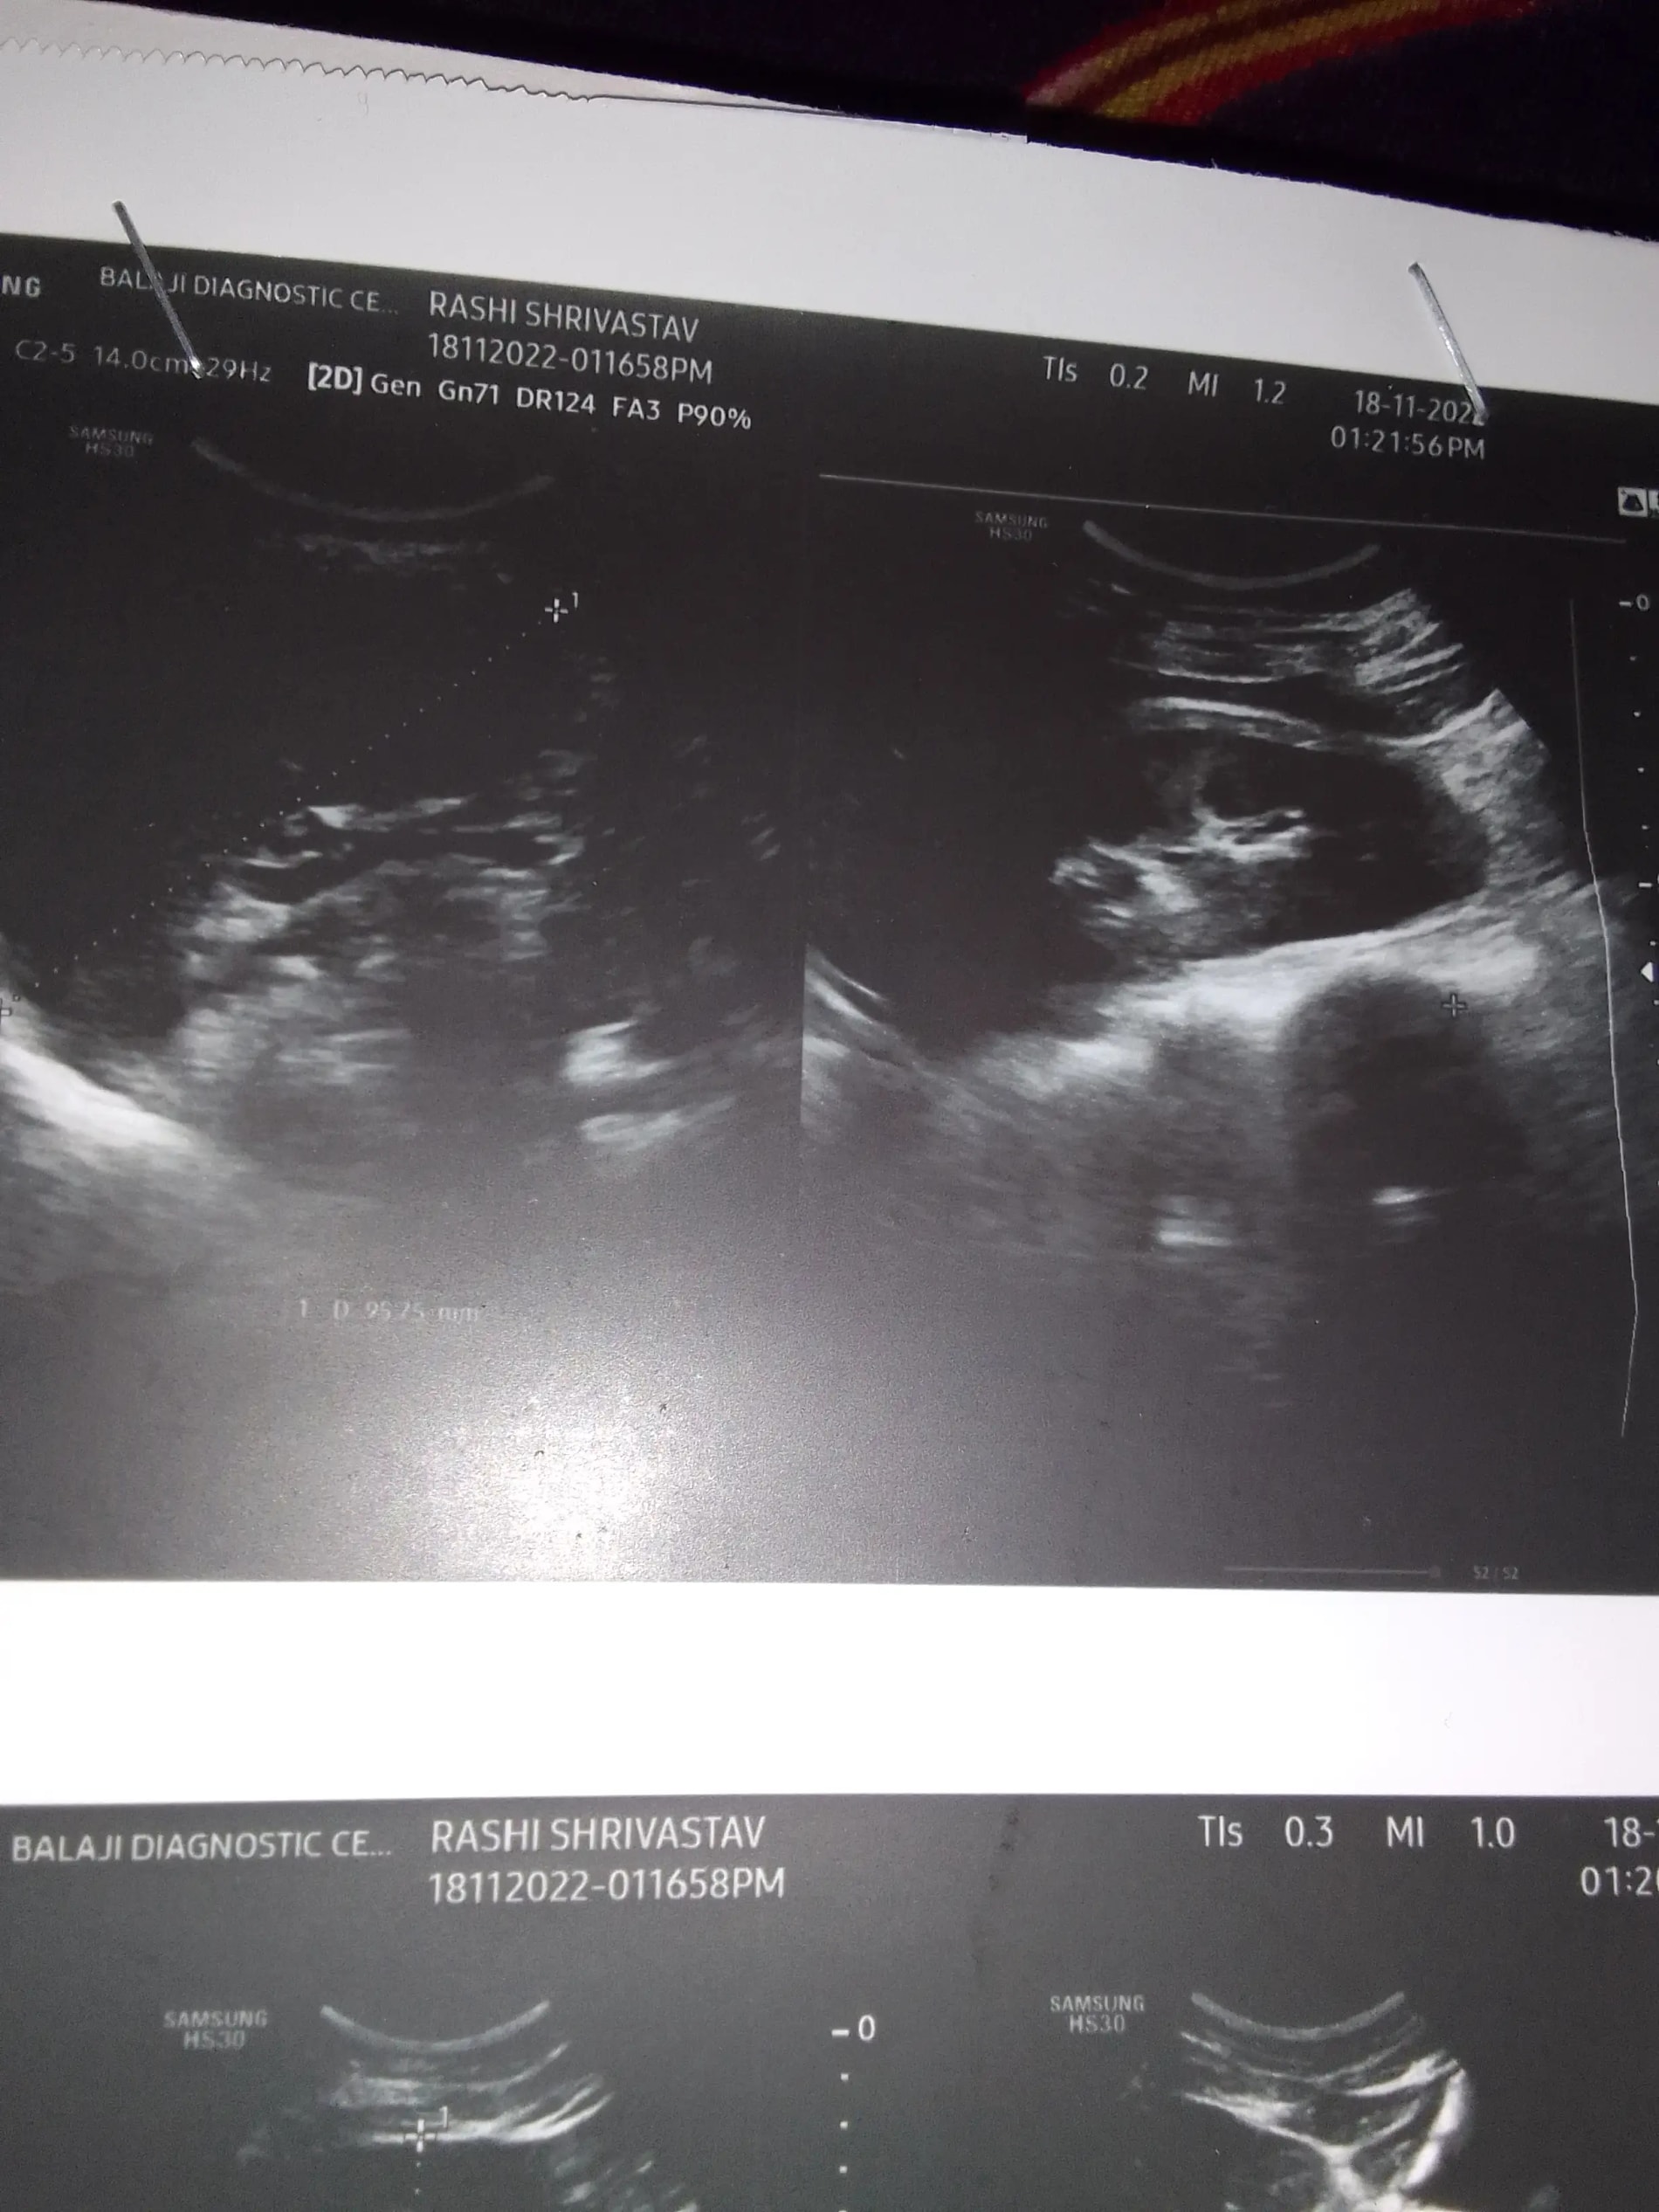

Q: Kya Bata sakti hai mere ultrasound se ki twins pregnancy hai ya one please agar pata chale to please koi bata do meko aisa lagta hai twins hai aap logon Ko kya lag raha mera ultrasound dekhne se

A: Written wala page share kijiye... See more

A: Iske sath Jo written report hai woh upload kro dear. ... See more